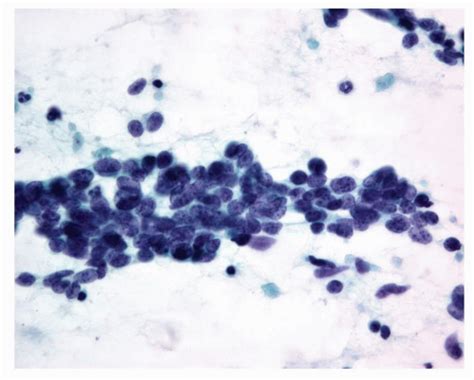

Squamous cell carcinoma can be a sneaky one, sometimes looking like other skin conditions, such as eczema or psoriasis. This is why biopsies are super important. Doctors take a small sample of the suspicious area and send it to a lab, where a pathologist examines the cells under a microscope. This is the only way to confirm whether it’s SCC and to what extent it has progressed. When SCC presents with pseudometastatic characteristics, the pathology report becomes even more crucial. The pathologist needs to carefully examine the sample to distinguish between local invasion (aggressive growth in the surrounding tissue) and actual spread of the cancer cells to other parts of the body. Treatment options for SCC vary depending on the stage of the cancer. They might include surgery to remove the tumor, radiation therapy to kill cancer cells, or topical creams for early-stage SCC. The good news is that most SCCs are curable, especially when detected early. Regularly checking your skin for any changes, especially if you have risk factors, is a good habit. Using sunscreen, seeking shade, and wearing protective clothing are excellent ways to reduce your risk. Understanding SCC and its behaviors, including its potential for pseudometastatic presentations, is essential for both prevention and proper medical care.